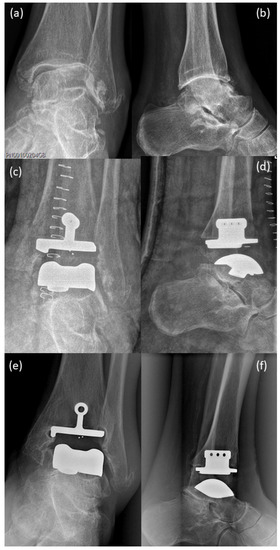

Arthrodesis and Defect Bridging of the Upper Ankle Joint with Allograft Bone Chips and Allograft Cortical Bone Screws (Shark Screw®) after Removal of the Salto-Prosthesis in a Multimorbidity Patient: A Case Report

3. Surgical Procedure

4. Postoperative Rehabilitation

5. Results